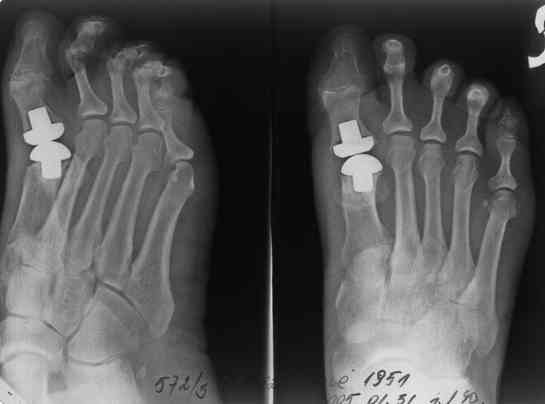

Уважаемые коллеги, Женщина 55 лет, живет в Литве, жалуется на сильные боли, отечность. Со слов больной по телефону, около года назад, предположительно по повду hallux valgus, было проведено эндопротезирование плюснефалангового сустава.

Можно предположить нестабильность одного или обейх компонентов эндопротеза (?) Что посоветовать, куда направить на очную консультацию, лечение?